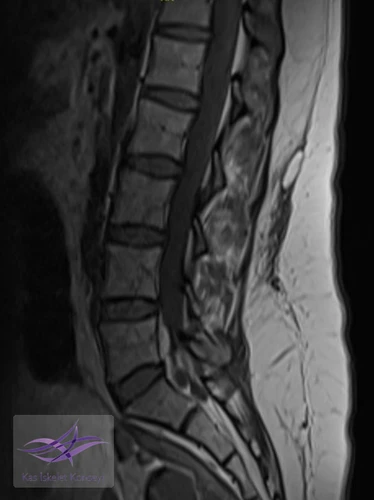

Resim 1. Sagital T1 ve T2 ağırlıklı lomber MR görüntülerinde subkutan doku ile torakolomber fasiyal planlar arasında psödokapsüllü sıvı toplanması izlenmekte (Morel-Lavallée lezyonu).

Morel–Lavallée lezyonu (MLL), subkutan doku ile derin fasya arasındaki ayrılma sonucu oluşan, hemolenfatik sıvı birikimiyle karakterize kapalı dekolman yaralanmasıdır. Trokanter majör çevresi en sık yerleşim yeri olmakla birlikte, lomber bölgedeki yerleşim son derece nadirdir ve diğer yumuşak doku ya da spinal patolojileri taklit edebilir.